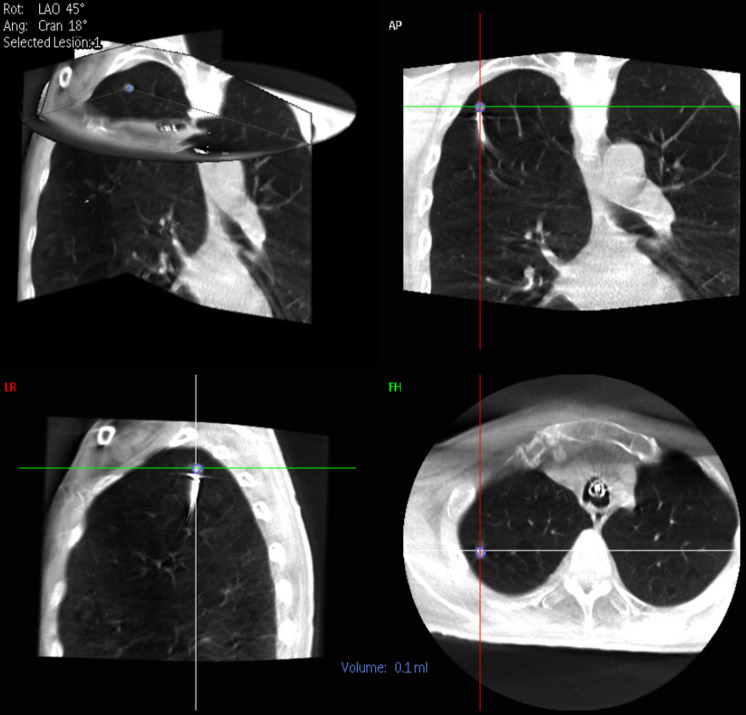

Figure 1.

Nodule segmentation view with 9 mm right upper lobe nodule selected in coronal, sagittal and axial views. LAO, left anterior oblique; AP, anterior to posterior; LR, left to right; FH, foot to head.